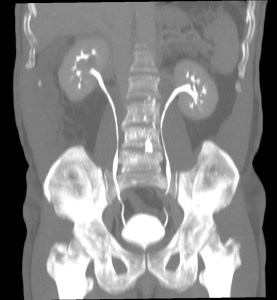

2. URINOMA.

Colección de orina extravasada al EPR y más allá que puede ser debida a obstrucción, espontanea o iatrogenia (accidente quirúrgico). La orina causa una una lipolisis de la grasa adyacente que posteriormente forma un saco fibroso que da origen al urinoma.

En la TC ve como:

- Colección homogénea de atenuación líquida.

- Forma irregular de distribución peripiélica o periureteral cuando la perforación es a este nivel.

- Engrosamiento septal y de la fascia perirrenal.

- Si son crónicos, los urinomas con el tiempo pueden descender siguiendo los límites del EPR y pueden presentan cápsula fibrosa que se realza con contraste en el TAC y que rodea al riñóm, simulando una nefromegalia.